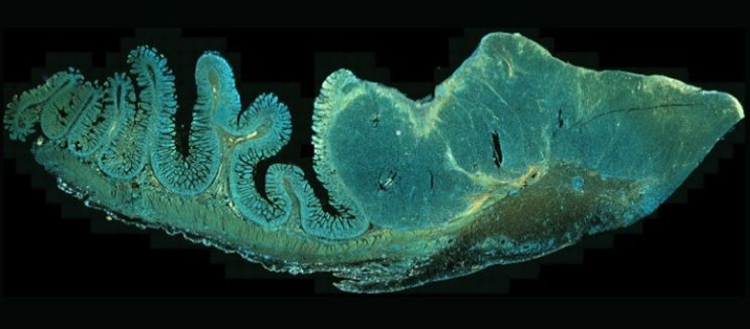

Analyse immunohistochimique d’une coupe de métastase intestinale de mélanome. © R.Merat, Neoplasia 2021; 23 (8): 775-782.

En clair, les scientifiques procèdent par étapes: ils et elles pratiquent sur un modèle murin des biopsies de tumeurs (ici des mélanomes) à différents stades de leur développement au cours des traitements. Grâce à des analyses immunohistochimiques – soit des coupes de tumeurs – ils et elles mesurent par une approche automatisée l’expression des protéines impliquées dans le mécanisme en jeu dans la réponse adaptative. «L’approche mathématique proposée est facilement applicable à des techniques de routine comme l’immunohistochimie et permet de valider in vivo la pertinence des mécanismes étudiés, même s’ils se produisent dans une minorité de cellules et de manière transitoire», se réjouit le chercheur genevois. Ainsi, les scientifiques peuvent non seulement valider dans l’organisme les mécanismes moléculaires qu’ils ou elles étudient, mais aussi l’impact de combinaisons thérapeutiques innovantes qui résultent de la compréhension de ces mécanismes «De même, nous pourrions utiliser dans les essais thérapeutiques cette approche comme marqueur prédictif de réponse aux combinaisons thérapeutiques qui cherchent à prévenir la résistance adaptative», poursuit-t-il.